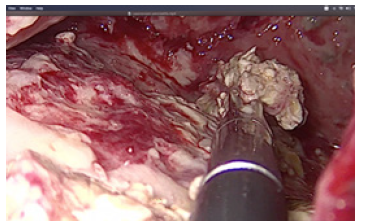

Debridement of necrotic material was performed by forceps and with a laparoscopic irrigation/suction device with evacuation of infected debris (Figures 4-6).